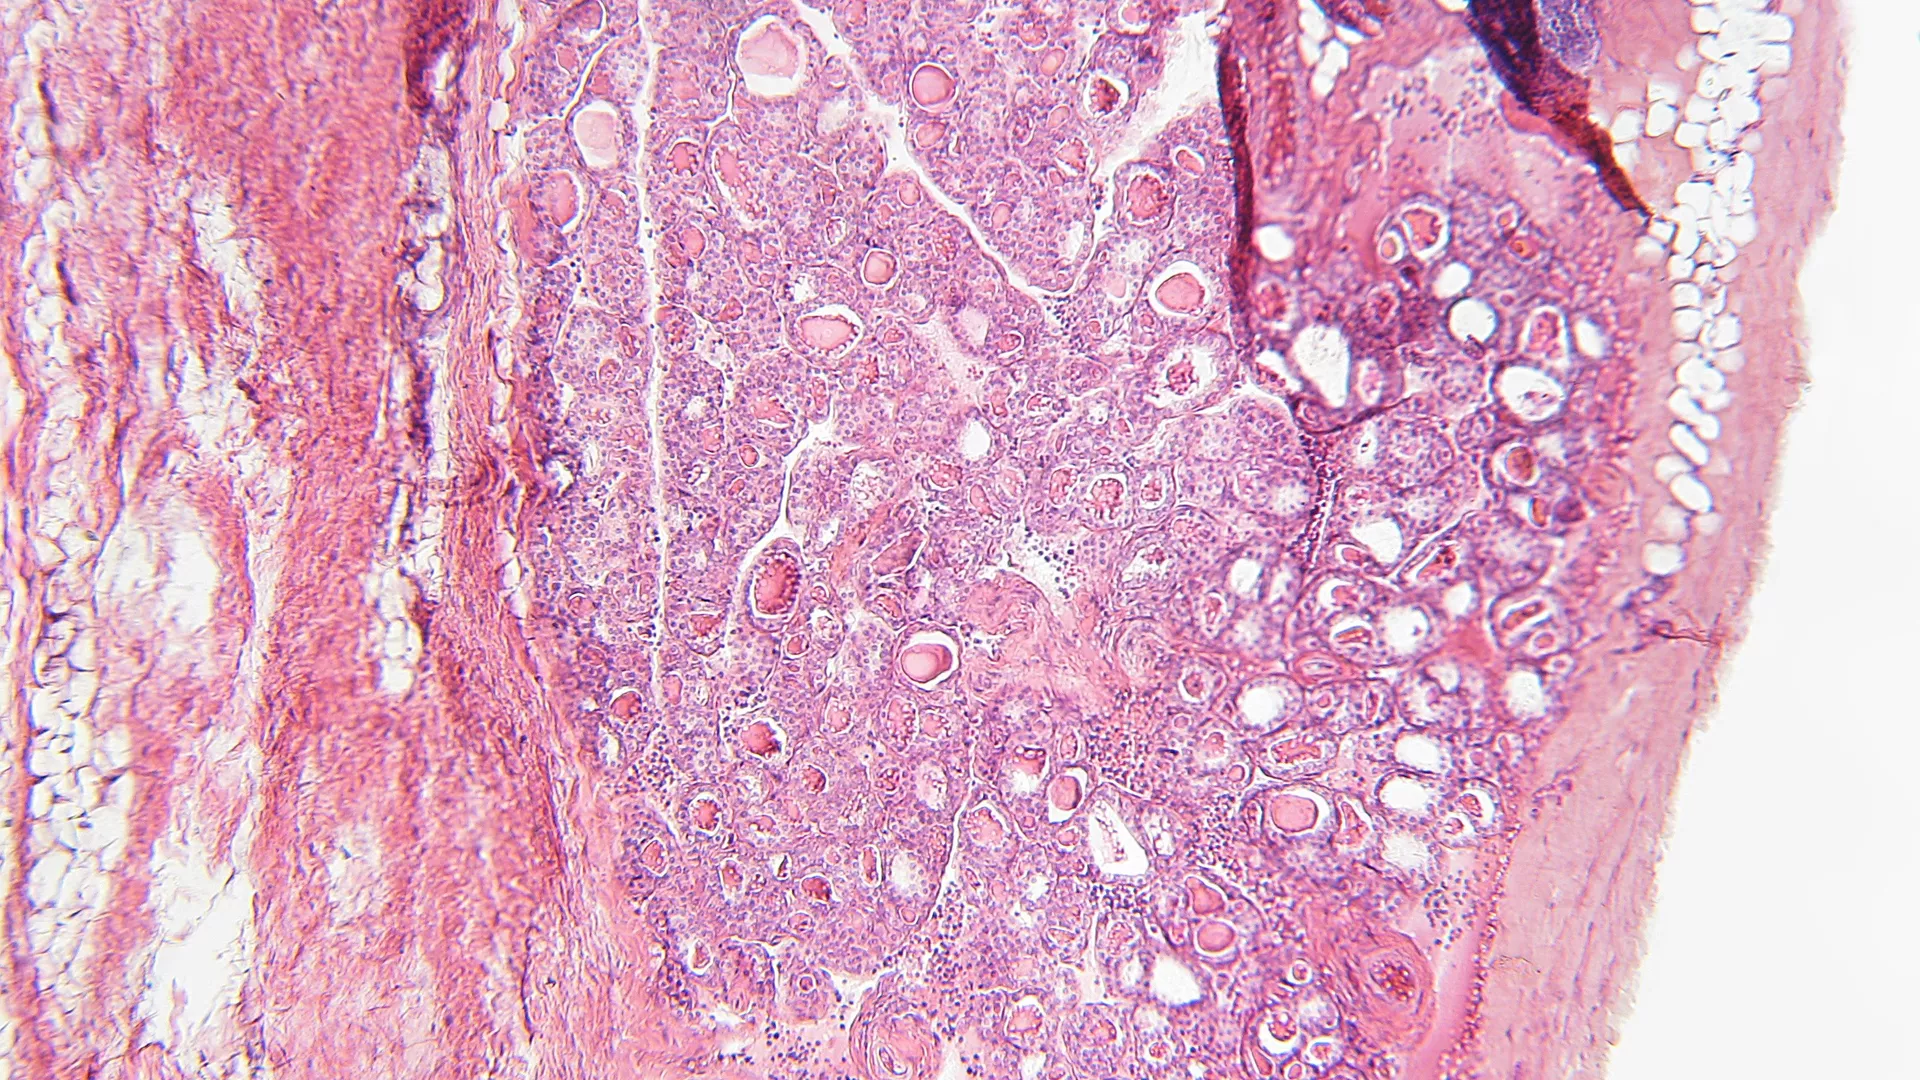

Rapacz-varkens met familiaire hypercholesterolemie ontwikkelen atherosclerotische laesies die sterk lijken op humane coronaire atherosclerose. Dit onderzoek cla